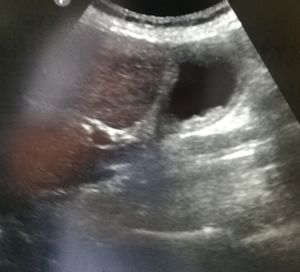

Diagnosis? Upper abdominal cross right

Ultrasound examination was on an empty stomach

Abdominal

Ultrasound

Sonography